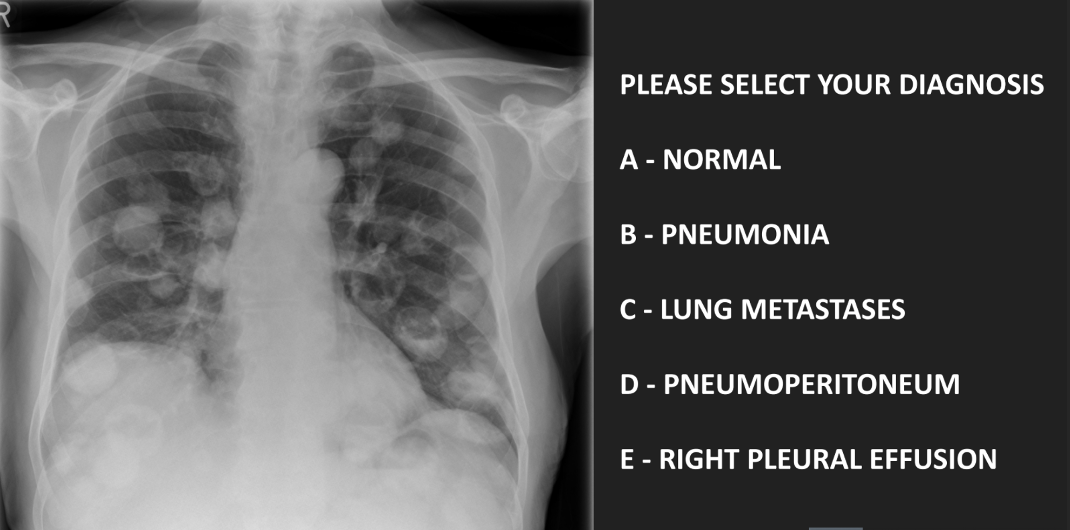

diagnose

C - lung metastases

• ‘Canon ball mets’

• Older patients

• Primary sites: bowel, renal cell, pancreatic and breast cancer